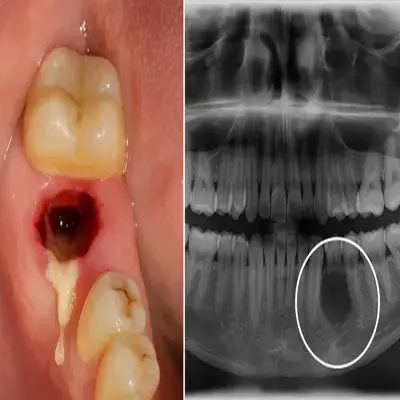

شدت عفونت، اندازه کیست، وضعیت استخوان فک و نتیجه تصویربرداری (مانند عکس OPG یا پریاپیکال) نقش تعیینکنندهای در انتخاب روش درمان دارند.

برای اینکه معاینه دقیقتر و تصمیم سریعتر گرفته شود، این نکات ساده کمک میکند: اگر تب، تورم منتشر، قفلشدن فک، مشکل بلع یا درد رو به افزایش دارید، منتظر نمانید و همان روز مراجعه کنید. اگر عکس پریآپیکال یا OPG دارید همراه ببرید؛ اگر ندارید، معمولاً همانجا تصویربرداری انجام میشود تا اندازه ضایعه و وضعیت استخوان فک مشخص شود.

تصمیم نهایی باید با معاینه و عکسبرداری (پریآپیکال یا OPG) گرفته شود.

تصمیم درست برای کشیدن دندان عفونتدار باید بر اساس معاینه و عکسبرداری (پریآپیکال یا OPG) انجام شود.

در بسیاری از موارد، کشیدن دندان کیستدار باعث از بین رفتن منبع اصلی عفونت میشود؛ اما این به معنی از بین رفتن قطعی کیست در همهی بیماران نیست. نتیجه نهایی به نوع ضایعه، اندازه آن و وضعیت استخوان اطراف بستگی دارد.

در تصویربرداری (OPG یا CBCT) نشانههای باقیماندن ضایعه دیده شود

اگر اطراف ریشه دندان کیست، گرانولوم یا آبسه دیده شده، مهمترین کار این است که با عکسبرداری (پریآپیکال یا OPG) و معاینه مشخص شود دندان قابل نگهداری هست یا نه.